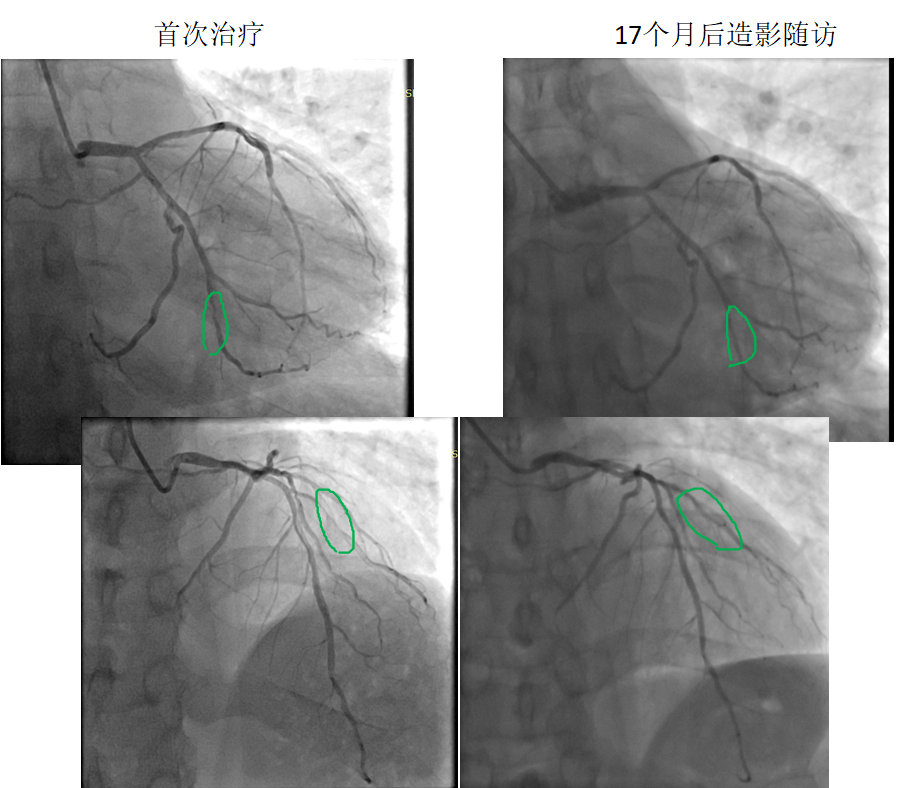

患者:男,38岁

病变部位: OM中远段95% ;D1近段90%

使用药物球囊:2.0 x 20mm; 2.0 x 20mm

17个月后造影

随访:OM中远段20% ;D1近段20%